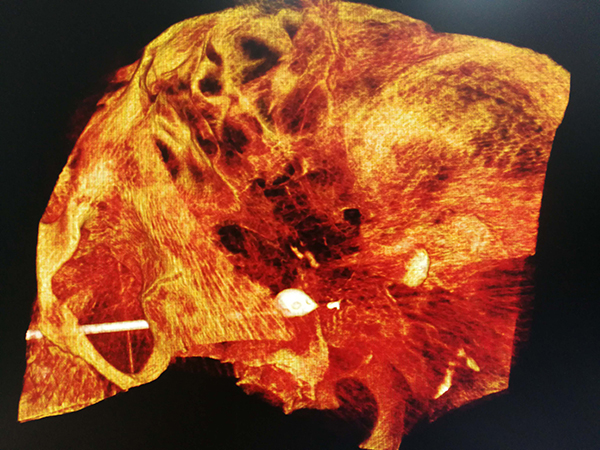

入院后經詳細詢問病史以及對病側三叉神經的痛覺、觸覺及運動等進行詳細評估,同時結合患者年近八旬、心肺功能差、營養(yǎng)狀況不良等因素,神經外科治療小組為患者實施了“三叉神經半月節(jié)微球囊壓迫術”。僅僅通過在病側口角外側約2.0cm皮膚穿刺,一次性成功將“微球囊”精準置入到位,微球囊壓迫半月節(jié)約3分鐘,撤出球囊及穿刺針,整個過程不超過十分鐘。術后困擾患者16年的疼痛消失了,使患者的臉上又有了笑容。

2.“微球囊”壓迫技術:是在影像引導下通過“微球囊”對三叉神經半月神經節(jié)進行短暫壓迫,從而阻斷痛覺神經傳導,最終達到祛除疼痛的治療效果。整個過程采用短暫舒適麻醉,不僅避免了局麻半月神經節(jié)射頻熱凝術所帶來的劇烈疼痛及相關風險,更無需開顱。微創(chuàng)不開顱、舒適無痛苦、手術時間短、風險相對較低。